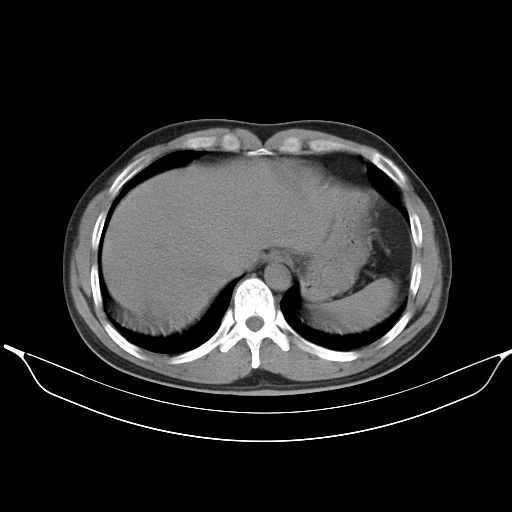

标题: CT25490:男,40岁,体检发现;无其它不适。 [打印本页]

标题: CT25490:男,40岁,体检发现;无其它不适。

2、轻度脂肪肝。

转移性肺肿瘤不排除,建议结合相关检查考虑

1、均为转移,原发灶不在肺内。2、肺癌肺转移。